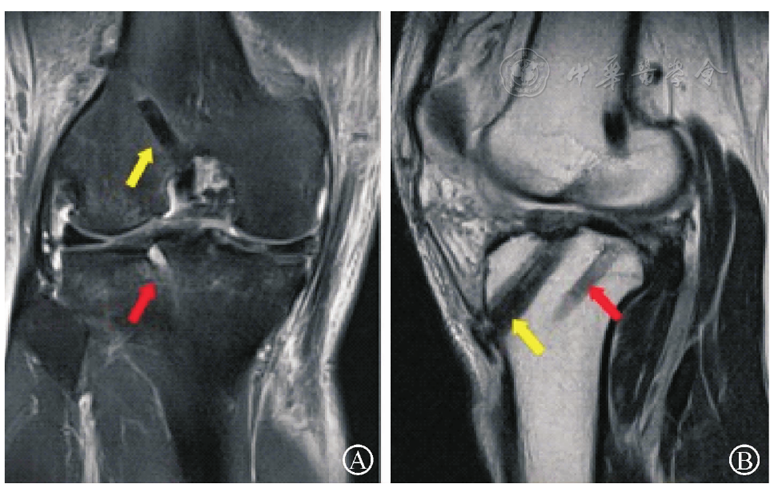

图4 经胫骨隧道pull-out技术修复LMPHRT(外侧半月板后根部撕脱)同时行ACL(前交叉韧带)重建术后MR影像。图A为膝关节冠状位MRI,红箭头示半月板胫骨隧道情况,内口位于外侧半月板根部;图B为膝关节矢状位MRI,黄箭头示ACL重建后胫骨隧道,红箭头示半月板胫骨隧道情况,内口位于外侧半月板根部